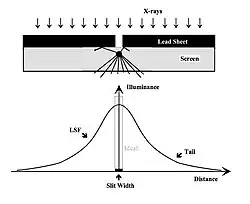

Fourier methods can be used to analyse the response of an imaging system to a square wave input using a narrow slit in a sheet of lead, for instance. Remember that a square wave is the equivalent of the sum of an infinite number of sine waves. The imaging of such a slit is illustrated in Figure 6.8 where the transmitted radiation is seen to excite fluorescence in an intensifying screen. The fluorescent light is emitted in all directions and the image of the slit therefore becomes spread out over a broader area than is ideal. The effect is seen in the illuminance profile which consists of a central peak, as expected, with tails extending around it. This type of profile is called the Line Spread Function (LSF). The effect on the slit’s image as a result is seen as a slight tinge of greyness around the slit’s edges to an extent given by the tails of the LSF. Better performance can therefore be seen as a narrowing in the LSF and a suppression of its tails.